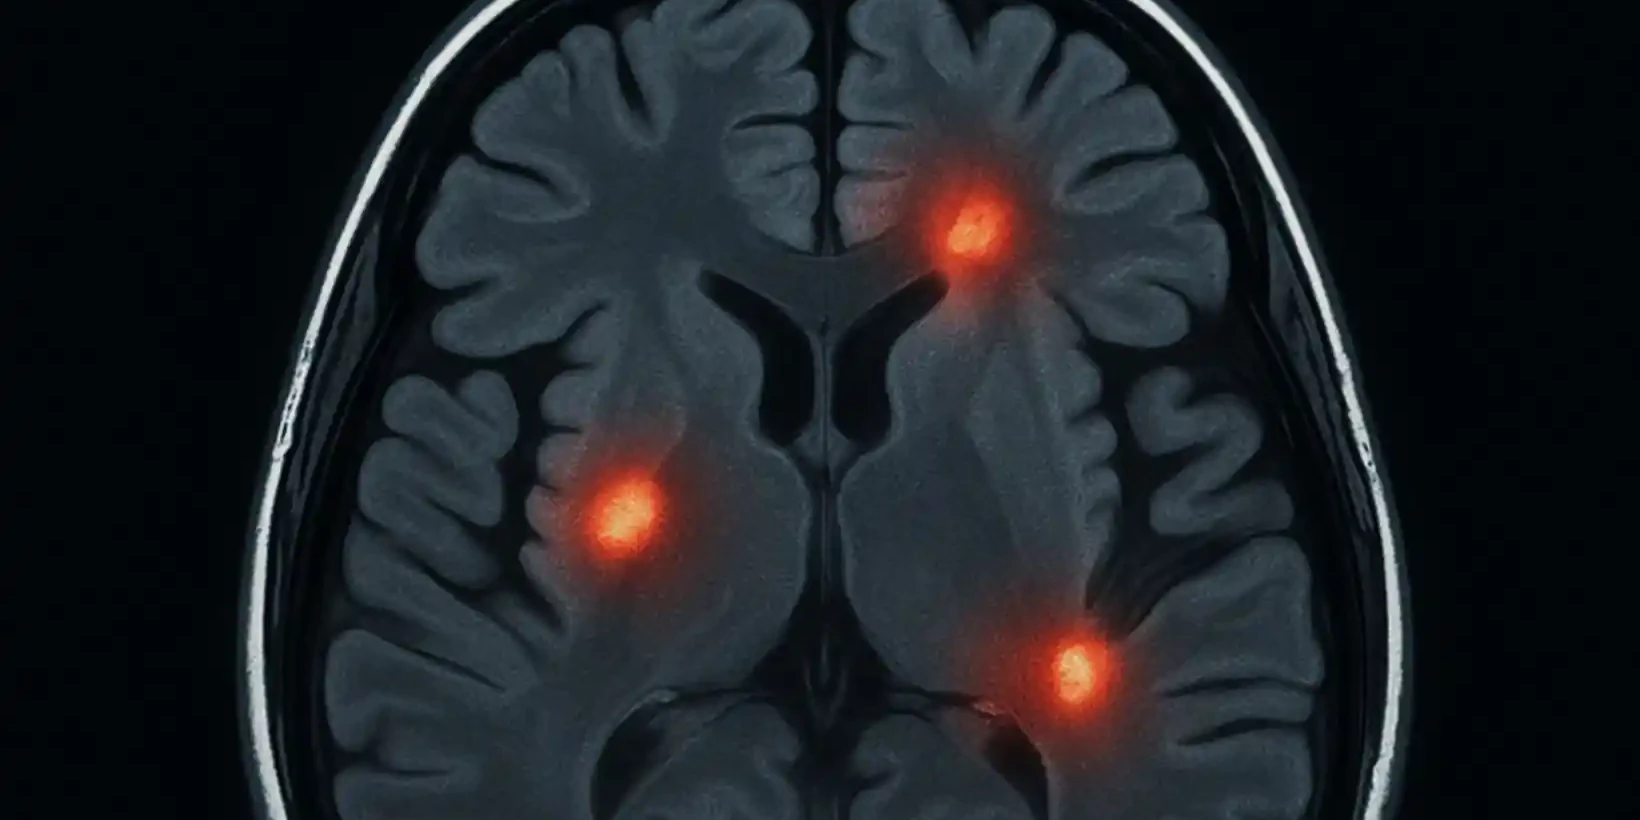

Migraine and Brain Lesions

What Are Brain Lesions? A brain lesion is an area where brain tissue is damaged. The damage can…

Brain Lesions: Causes, Symptoms, Treatments

Brain lesions are areas of damage in the brain tissue, and understanding them is crucial for your…